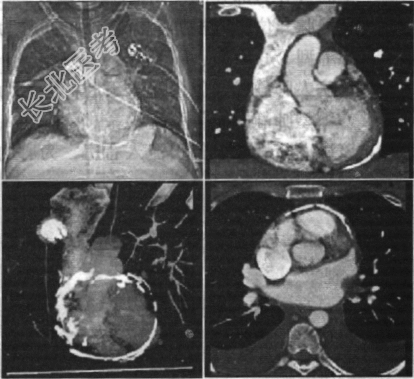

- 多项选择题58岁男性患者,曾患肺结核, 心悸气促乏力,下肢肿胀半年余, 胸部CT扫描如下图,描述正确的是

A、心包钙化显著时也可称之为“盔甲心”

B、心包钙化多见于结核,X线、CT、超声为常用检查方法

C、超声心动检查见心包不规则增厚、回声增强,多以房室交界处最为显著,厚度多大于3mm,有僵硬感,心脏的局部或整体活动受限,室壁舒张受限尤其明显

D、MRI显示增厚的心包较X线、CT优越,但是对心包钙化不敏感

E、考虑为缩窄性心包炎